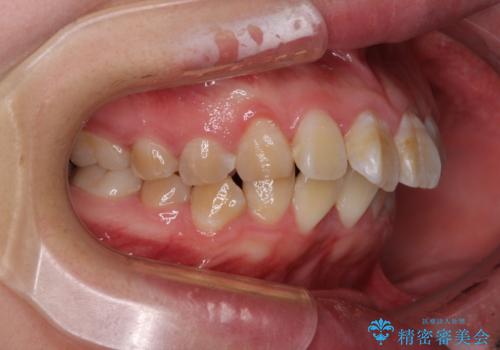

- 口元の閉じにくさと、前歯のでこぼこの歯並びを気にして来院された患者様です。

口元を積極的に引っ込めるために、上下左右の小臼歯計4本を抜歯することとしました。

4本の歯を抜歯したことで、飛び出していた口元が引っ込み、横顔が大きく改善されました。